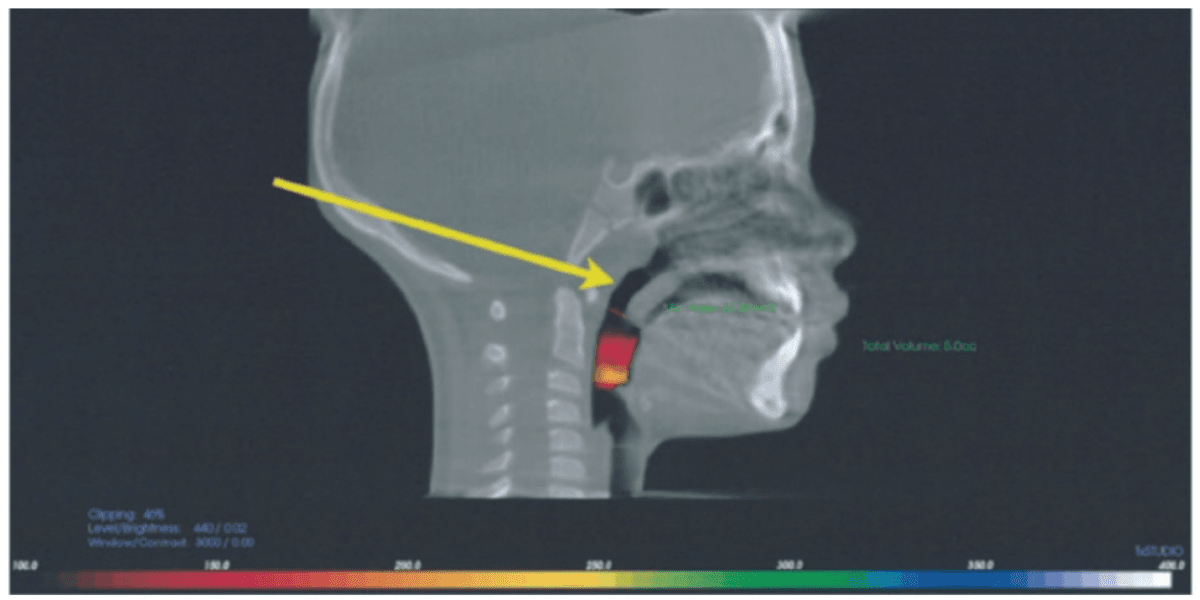

Decompressing the TM joints with a removable lower appliance at a physiologic position (sibilant phoneme registration/phonetic bite) has been shown to increase pharyngeal airway volume and decrease collapse. It also allows for stabilization of the TM joints, reducing pressure on the mandible without any pressure on the frontal bone.46,47 This Tandem Bow technique was explained in a previous case study titled, “Pediatric severe apnea/obesity/TMD/headache-Class III” in Orthodontic Practice US, May/June 2016, Volume 7, No. 3, pages 20-24. The 10-year-old patient who had been on CPAP for 5 years with an AHI of 118 was reduced to an AHI of 3 in 8 weeks and was able to discontinue her PAP therapy (Figure 8). Forward head posture corrections can be seen with decompression of the TM joints utilizing this technique (Figure 9). This technique is explained in Chapter 7 of Sleep Disorders in Pediatric Dentistry: Clinical Guide on Diagnosis and Management, edited by Dr. Edmund Liem, and published by Springer. Chapter 7 is authored by Dr. Edmund A. Lipskis, and titled, “Orthodontic and Dentofacial Orthopedic Treatment Strategies for Pediatric Sleep Disorders.” Advancing the entire maxilla is necessary to protract the palatine bones to increase the volume of the velopharynx (the narrowest part of the airway) (Figure 10).